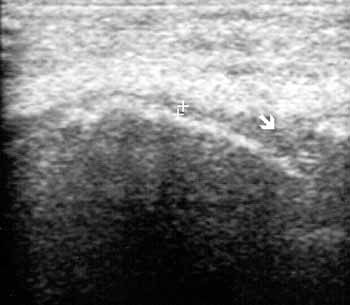

Рис. 7. Ревматоидный артрит, III стадия; резкое истончение гиалинового

хряща медиального мыщелка (+), наличие над ним жидкости (стрелка), уплощение

суставной поверхности.